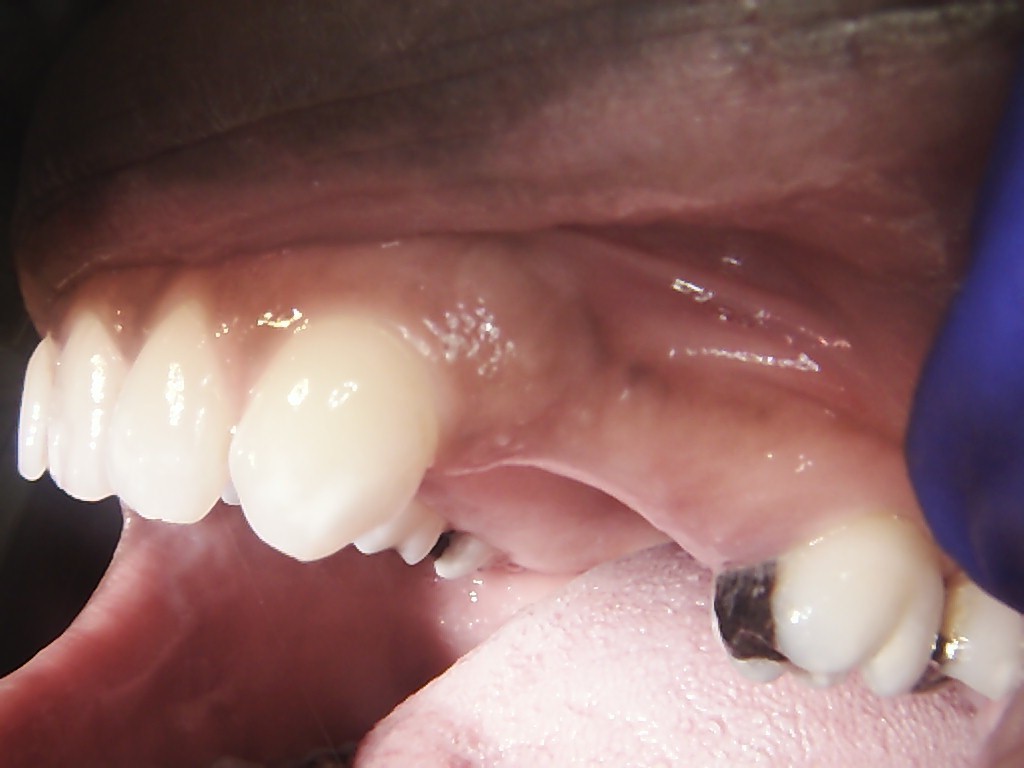

Examples of our work.

Multiple Teeth case with Sinus Lift